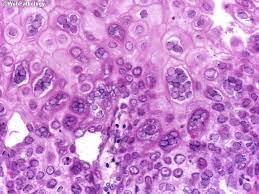

Cytomegalovirus esophagitis is a form of esophagitis associated with cytomegalovirus. Herpes esophagitis is a viral infection of the esophagus caused by herpes simplex virus (hsv). Herpes esophagitis is a viral infection of the esophagus caused by herpes simplex virus (hsv). Symptoms include dysphagia, upper abdominal pain, diarrhea, nausea, vomiting, and sometimes hematemesis. Very few cases of a multiple viral infection have been reported. Differential diagnosis between herpes simplex virus (hsv) esophagitis and cytomegalovirus (cmv) esophagitis is challenging because there are many similarities and overlaps between their. Common forms of esophagitis include reflux esophagitis, infectious esophagitis, pill esophagitis candida esophagitis (see the image below) is the most common type of infectious esophagitis. Swallowed food and liquids normally pass through it. Eosinophilic esophagitis attributed to gastroesophageal re. Infective esophagitis is a rare disease, affecting mostly immunocompromised patients. Healing and relapse of severe peptic esophagitis after treatment with omeprazole. Esophagitis can occur from irritation from toxic or abrasive materials ingested or from gastric reflux. The esophagus is a tube composed of a mucosal lining, and longitudinal and circular smooth muscle fibers.

Peptic strictures cause a gradually progressive dysphagia for solid foods. Very few cases of a multiple viral infection have been reported. Symptoms include dysphagia, upper abdominal pain, diarrhea, nausea, vomiting, and sometimes hematemesis. Cytomegalovirus esophagitis is a form of esophagitis associated with cytomegalovirus. Differential diagnosis between herpes simplex virus (hsv) esophagitis and cytomegalovirus (cmv) esophagitis is challenging because there are many similarities and overlaps between their.

Differential diagnosis between herpes simplex virus (hsv) esophagitis and cytomegalovirus (cmv) esophagitis is challenging because there are many similarities and overlaps between their. Esophagitis can cause painful, difficult swallowing and chest pain. Healing and relapse of severe peptic esophagitis after treatment with omeprazole. Esophagitis can occur from irritation from toxic or abrasive materials ingested or from gastric reflux. Causes of esophagitis include stomach acids backing up into the esophagus, infection, oral medications and allergies. The latter can occur frequently during anesthesia or deep sedation. Very few cases of a multiple viral infection have been reported. Herpes esophagitis is a viral infection of the esophagus caused by herpes simplex virus (hsv). Esophagitis may cause odynophagia and even esophageal hemorrhage, which is usually occult but can be massive. We present a case of combined cytomegalovirus. Eosinophilic esophagitis attributed to gastroesophageal re. Swallowed food and liquids normally pass through it. Esophagitis, also spelled oesophagitis, is a disease characterized by inflammation of the esophagus.

Cytomegalovirus esophagitis is a form of esophagitis associated with cytomegalovirus. Peptic strictures cause a gradually progressive dysphagia for solid foods. Cobblestone esophagitis (эзофагит со слизистой булыжной мостовой). Herpes esophagitis is a viral infection of the esophagus caused by herpes simplex virus (hsv). This condition occurs in the setting of patients with a weakened immune system who are susceptible.